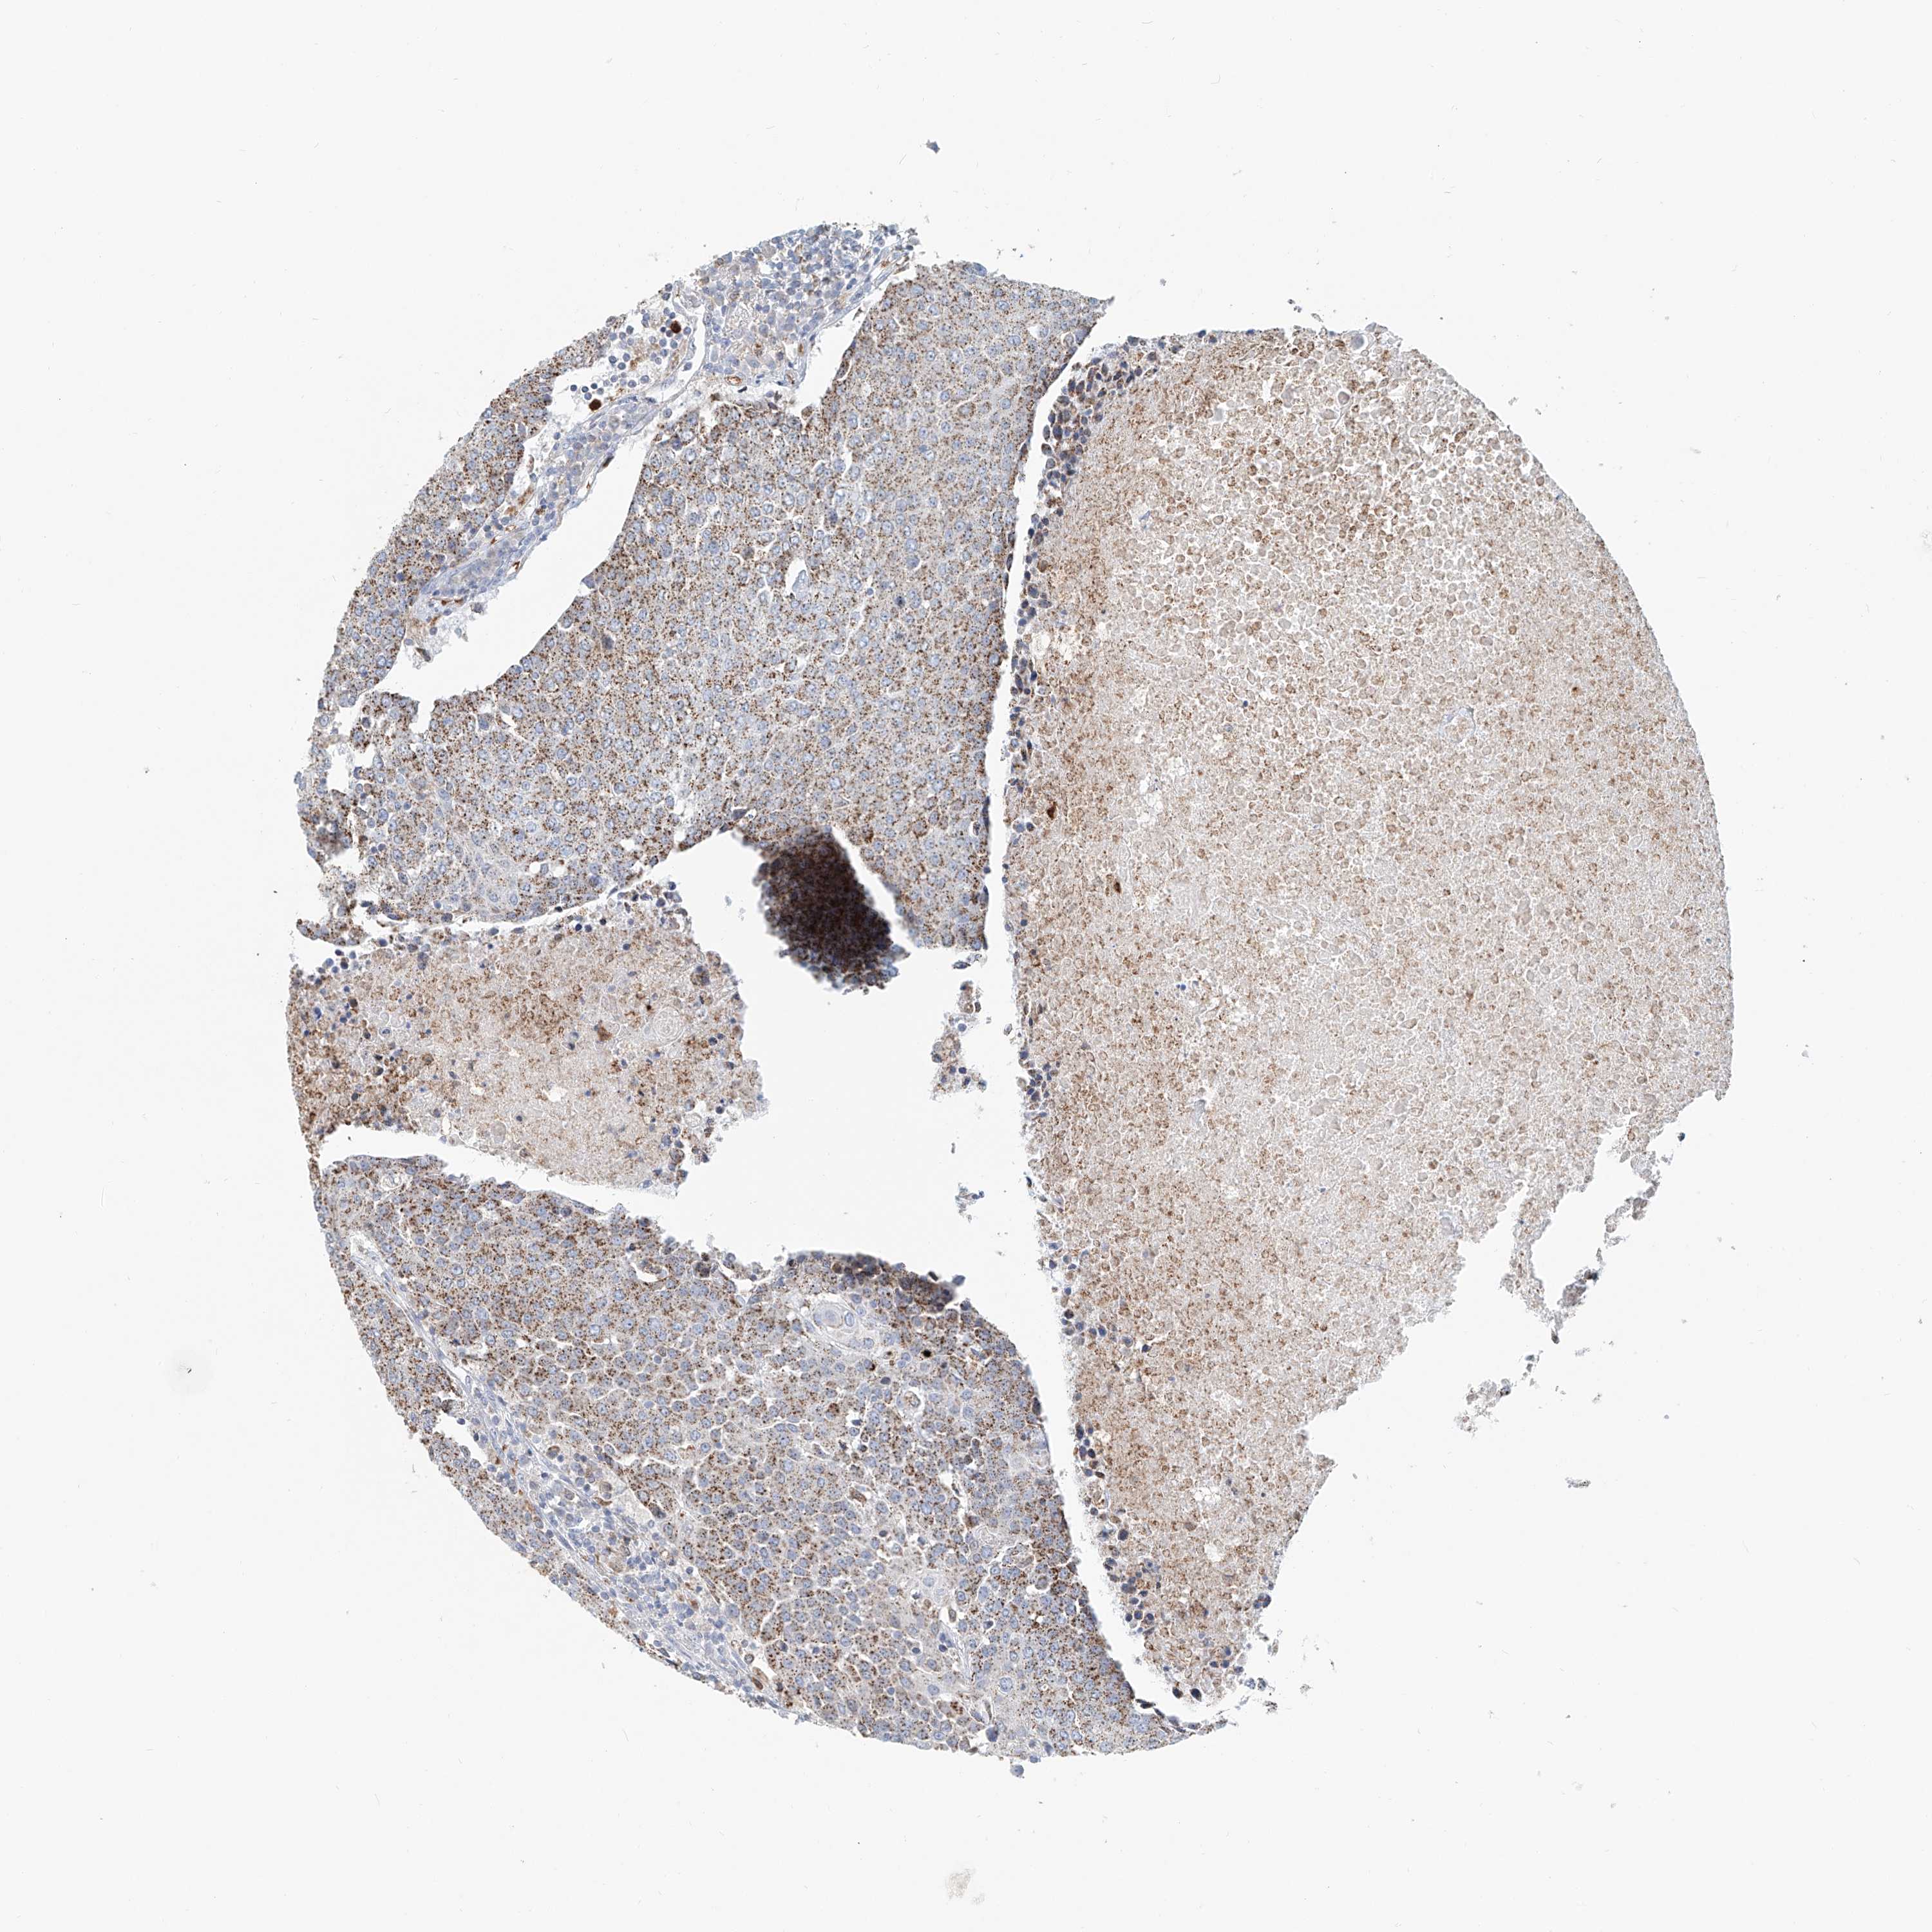

UROTHELIAL CANCER - Protein expressioni

A mouse-over function shows sample information and annotation data. Click on an image to view it in a full screen mode. Samples can be filtered based on level of antibody staining by selecting one or several of the following categories: high, medium, low and not detected. The assay and annotation is described here.

Note that samples used for immunohistochemistry by the Human Protein Atlas do not correspond to samples in the TCGA dataset.

Antibody stainingi

Antibody staining in the annotated cell types in the current human tissue is reported as not detected, low, medium, or high, based on conventional immunohistochemistry profiling in selected tissues. This score is based on the combination of the staining intensity and fraction of stained cells.

Each image is clickable and will lead to virtual microscopy that enables deeper exploration of all samples and also displays staining intensity scores, fraction scores and subcellular localization as well as patient and tissue information for each sample.

Antibody HPA029412

Antibody CAB034366

Urothelial carcinoma, Low grade

Urothelial carcinoma, High grade